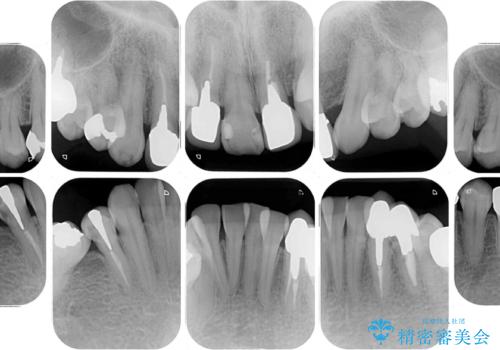

- 非対称な前歯や奥歯の目立つ銀歯を気にして来院された患者様です。

左上前から2番目の歯は、以前裏側に位置していたことから抜歯をされていましたが、前歯の非対称が長年気になっているとのことでした。

矯正治療によって前歯にスペースを作り、左右対称となるようにオールセラミッククラウンにて補綴治療を行うとしました。

他にも奥歯の咬み合わせに問題があったので、全顎的な矯正治療を行い、前歯以外にも口を開けたときに目立つ奥の銀歯をセラミッククラウンにて補綴治療を行うこととしました。